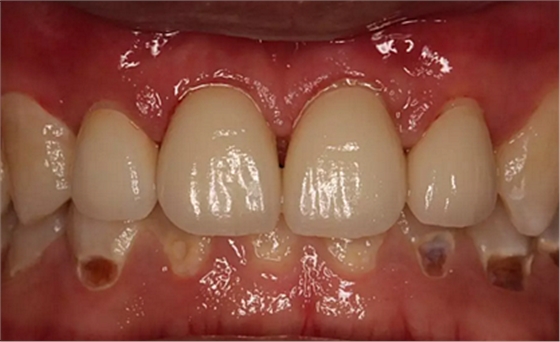

第5次復診的時候,終于讓我們4個兄弟恢復了正常的容顏。

現(xiàn)在剩下的任務就是為我其他的兄弟姐妹們治療了。需要做根管的做根管,需要做冠的做冠,需要樹脂充填的做樹脂充填。前前后后主人帶我們進行了12次的復診,歷時6個月,現(xiàn)在的我們是這樣的